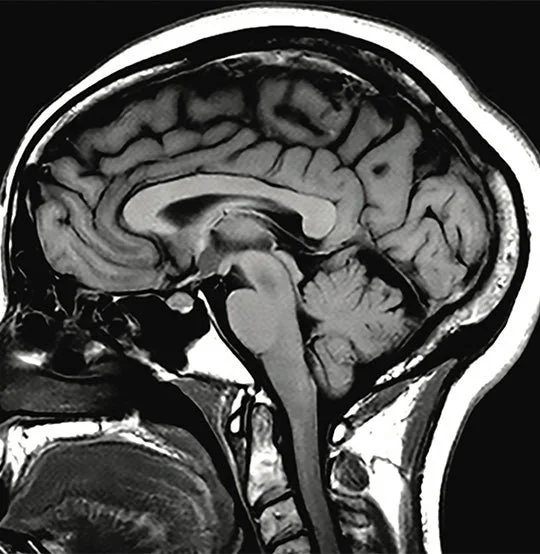

Review your medical imaging results one-on-one with a radiologist including pertinent findings in the report, their correlation on imaging and potential clinical impact